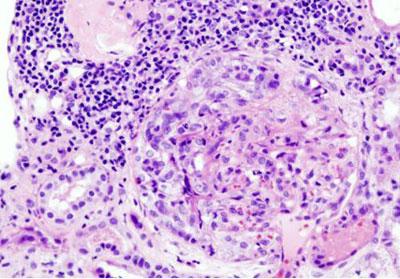

У пациента проводится забор небольшого кусочка ткани для цитологического и гистологического исследования. Это поможет определить вид сформировавшейся опухоли.